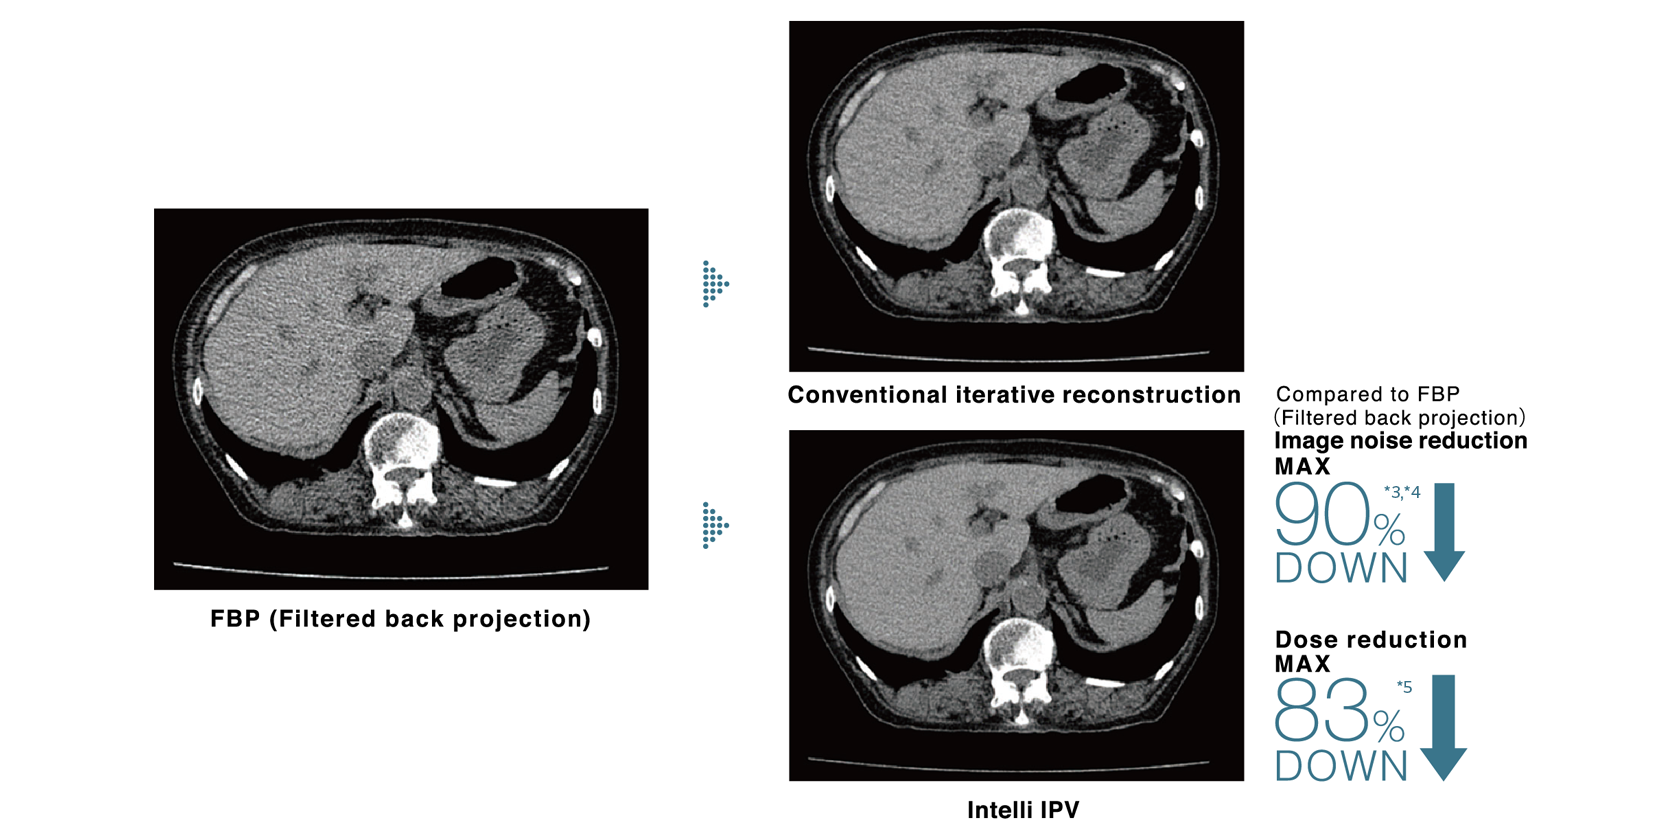

Our iterative reconstruction method, Intelli IPV, provides images that maintain their natural texture even at high noise reduction rates and their excellent visibility even at low doses, and does not require a dedicated operating room or additional hardware.

While adjusting the texture at a uniform ratio from high frequency to low frequency, the physical properties that affect visibility are made as close as FBP.

- *3 It is obtained in the abdominal region.

- *4 Compared to FBP. It was measured using Intelli IPV intensity level Strong5 and tested to a water phantom. Depending on the clinical task, patient size, anatomic location, and clinical examination, the effect obtained may be smaller.

- *5 Compared to FBP. It was measured at 0.625 mm slice thickness using Intelli IPV intensity level Strong5 and tested to MITA CT IQ phantom CCT189, Phantom Laboratory using the model observer method results. Depending on the clinical task, patient size, anatomic location, and clinical examination, the effect obtained may be smaller.